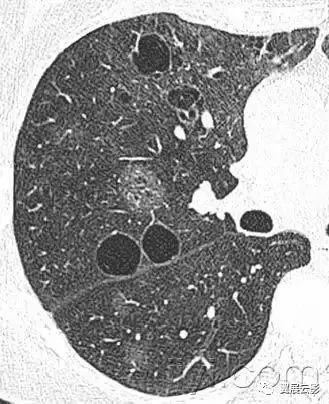

十六、肺大疱:

病理:直径大于25px(通常为几个cm)的含气腔隙,边界清晰,薄壁(小于1mm)。肺大疱常见临近肺的气肿性改变。

平片和CT:肺大疱表现为圆形的局部透亮影或者低密度,直径25px或者更大,薄壁。常可见多发肺大疱及其他肺气肿的表现(小叶中心型和间隔旁型)